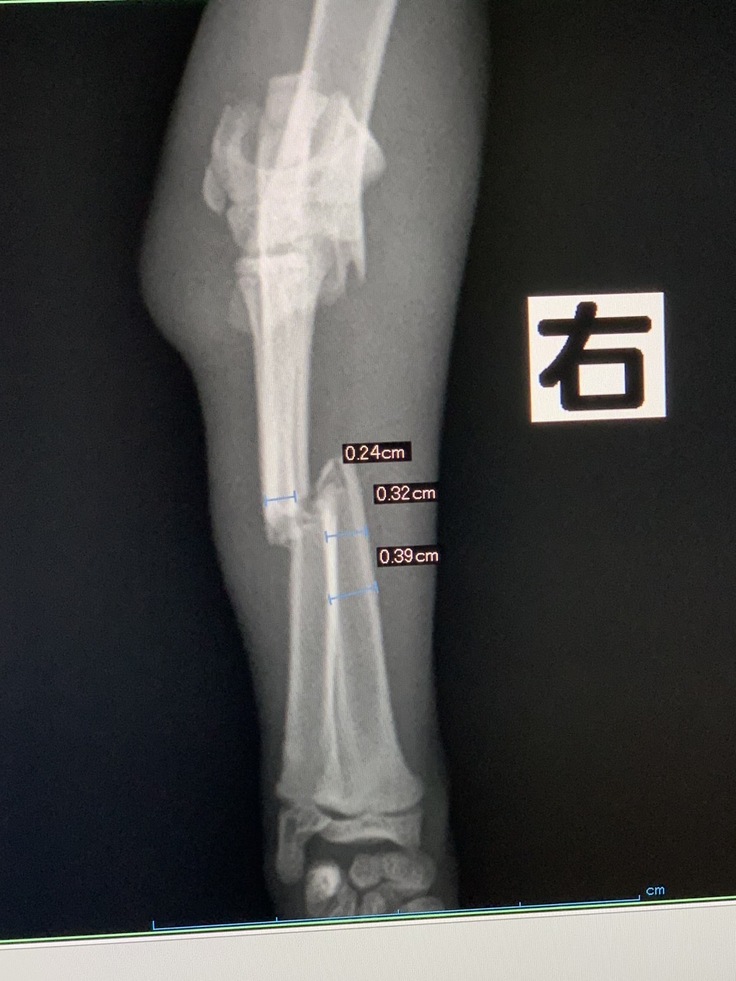

両手両足4本骨折…小さな命がんばれ!

両足両手4本きれいに折れていました…

他に損傷もなく、考えたくはないけど、もしかしたら虐待され捨てられたのかもと…

800gの小さな命